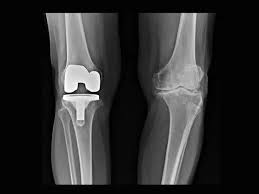

Knee Replacement

Knee replacement, also known as knee arthroplasty, is a surgical procedure performed to relieve pain and restore function in severely diseased knee joints. It involves removing damaged cartilage and bone...